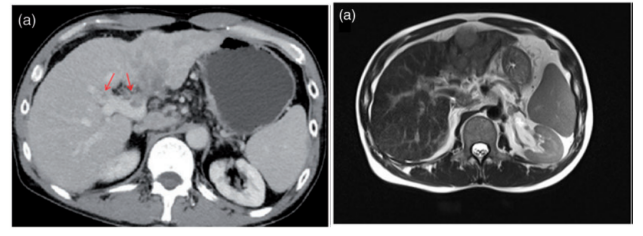

CT扫描和磁共振成像(MRI)显示在右侧前叶、左侧和尾状叶弥漫性动脉高血管/门静脉洗脱团块,侵犯主干、右侧前叶、左侧门静脉、左肝静脉和下腔静脉。肝硬化,门脉高压,脾肿大,腹膜后淋巴结也被观察到。

患者接受肝细胞癌RFA和瘤内注射rhAd5(1.0*10^12病毒颗粒,1次),此外,术后每3周静脉给予帕博利珠单抗(每次200 mg) 1次。恩替卡韦常规用于抑制HBV复制。治疗6周后复查肿瘤标志物,AFP和PIVKA-II分别降至10.090 ng/mL和25.00 mAU/mL。治疗5个月后复查增强CT,肿瘤及肿瘤血栓较治疗前明显缩小。再次MRI增强检查发现肝左叶及尾状叶斑片状异常信号影明显变小,肿瘤血栓消失或缩小。

在检查了病人的情况后,一个多学科小组决定进行左半肝切除术以根治性切除肿瘤。结合术中彩色多普勒超声及肝活检结果,经患者及家属同意,行肝左外侧叶切除术。门静脉左支开放,未见肿瘤血栓形成。术中冰冻切片检查及术后病理标本未见肿瘤;门脉区仅观察到结节性肝硬化和慢性炎症。术后18个月随访,影像学及肿瘤标志物检测均未见复发。